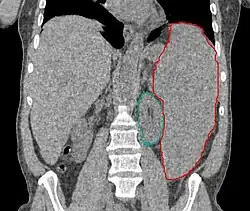

Enlarged spleen due to myelodysplastic syndrome; CT scan coronal section, spleen in red, left kidney in green